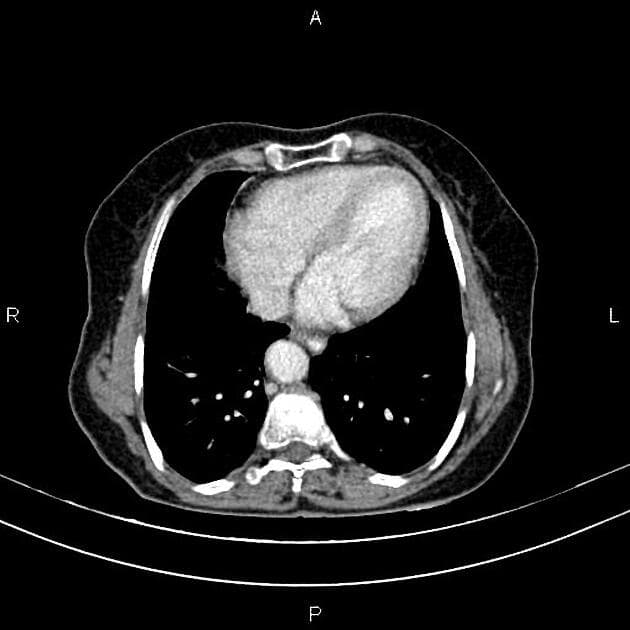

- Một khối ngấm thuốc kích thước 28 x 20 x 22 mm nằm ở phần trên của hệ thống đài bể thận phải.

- Khối u tế bào biểu mô niệu quản thận phải đã được chứng minh bằng giải phẫu bệnh, không có bệnh lý hạch vùng (regional lymphadenopathy) hay di căn rõ trên hình ảnh.

- Trên cắt lớp vi tính (CT), tổn thương thường có mật độ mô mềm với mức độ ngấm thuốc nhẹ, thường thấp hơn đáng kể so với nhu mô thận hoặc ung thư tế bào ống thận.

Ung thư tế bào biểu mô niệu quản thận khởi phát từ biểu mô chuyển tiếp của đài bể thận và được phân loại mô học là một dạng ung thư biểu mô niệu quản. Bệnh chiếm khoảng 5–10% các ung thư thận, hiếm gặp hơn nhiều so với ung thư tế bào ống thận. Trên CT có cản quang, tổn thương điển hình là khối mô mềm nhỏ trong đài bể thận với mức độ ngấm thuốc nhẹ đến trung bình. Do vị trí và đặc điểm ngấm thuốc không rõ rệt, khối u dễ bị bỏ sót, đặc biệt khi không có giãn đài bể thận. Chẩn đoán thường được nghĩ đến ở bệnh nhân tiểu máu không đau, nhất là những người có yếu tố nguy cơ như hút thuốc hoặc tiếp xúc nghề nghiệp với amin thơm. Chẩn đoán xác định cần dựa vào sinh thiết hoặc mẫu mô sau phẫu thuật. Điều trị chủ yếu là cắt thận – niệu quản toàn bộ kèm cắt vạt bàng quang, tùy theo giai đoạn bệnh và tình trạng bệnh nhân.